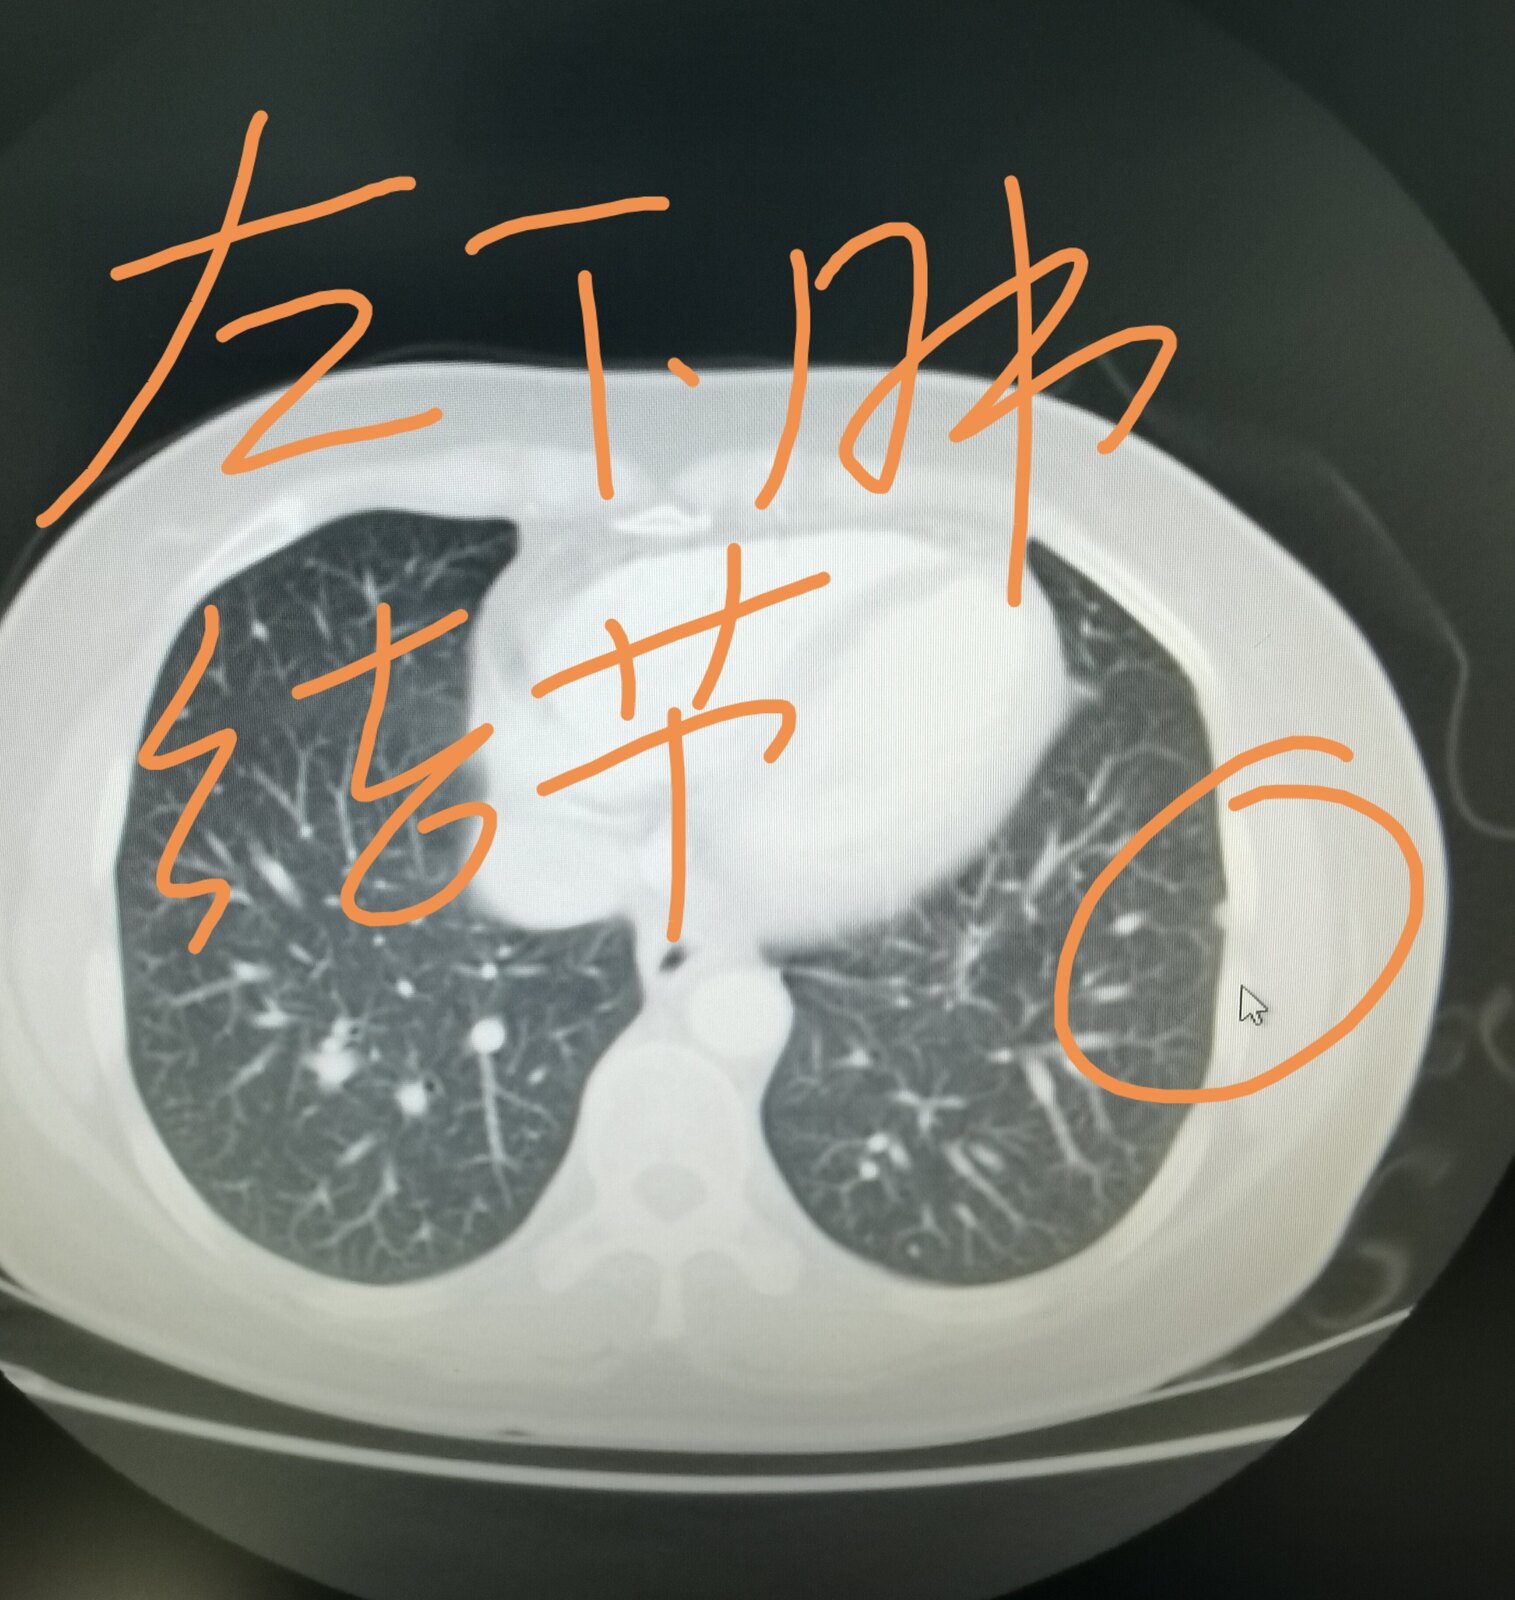

今天有一台手术就属于这个情况,我把这位患者的片子给大家发在下面,这是一位51岁的女士,三个月前因为咳嗽在当地医院拍片子,发现了肺部占位,她过来找我,想在我这里治疗。我给她进行了系统的检查,当时发现左上肺这个占位侵犯了纵隔,纵隔淋巴结增大,考虑转移,直接手术效果不好。这位女士好在其他部位并没有转移,我给她安排了穿刺,病理显示是一个肺腺癌,做基因检测,存在EGFR敏感突变,她吃了两个月的靶向药,肿瘤和淋巴结都缩小了。今天给她做的手术,手术过程是很困难的,里边粘连的比较严重,血管也很难分离,但过程很顺利,现在正在密切观察中。她除了左上肺这个病变之外,左下肺还有一个结节,吃靶向药也没有减小,术中探查的时候,考虑是一个肺内淋巴结,也给她一并切了下来。